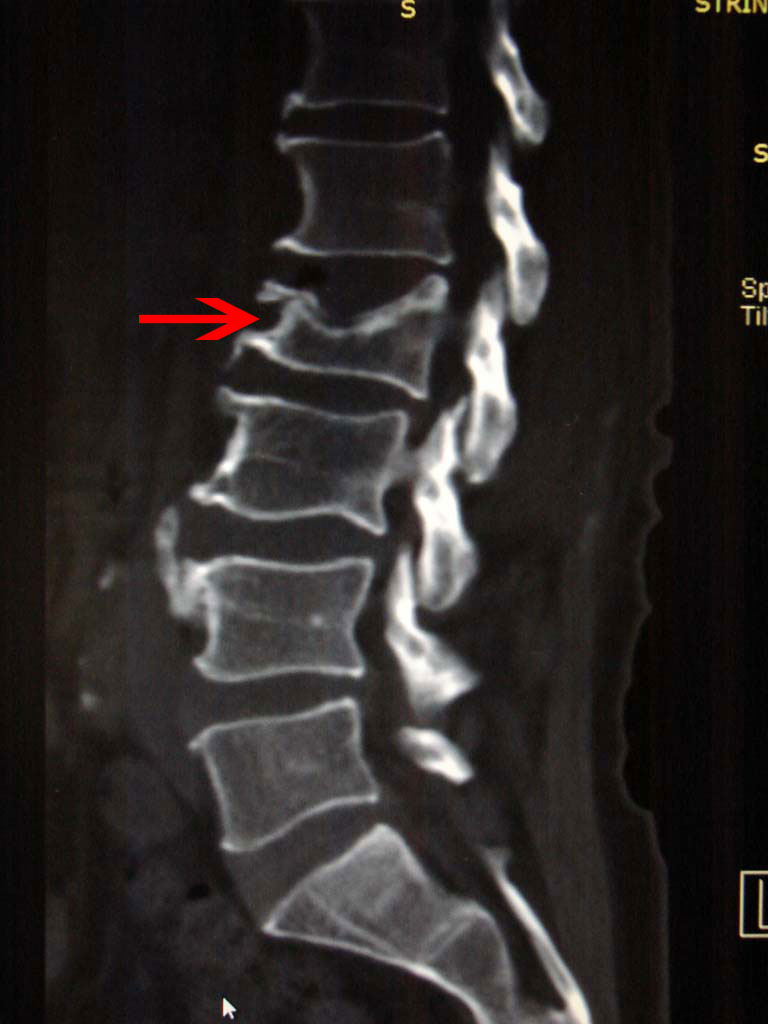

Ο πάσχων φόρεσε υψηλή ζώνη οσφύος για την αντιμετώπιση του κατάγματος, όμως ο νέος έλεγχος δια – αξονικής τομογραφίας στις 12/01/2017 έδειξε περαιτέρω καθίζηση του κατάγματος.

- Πλάγια λήψη: παρατηρείται περαιτέρω καθίζηση του σώματος του 2ου οσφυϊκού σπονδύλου